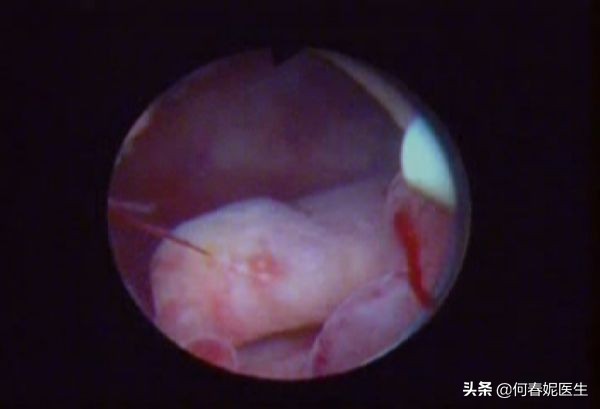

宫腔镜手术是子宫内膜息肉诊断和治疗的「金标准」。